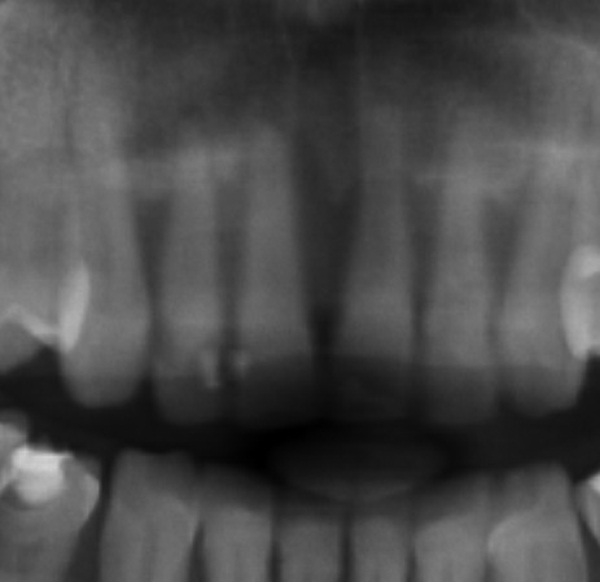

Bogata w płytki i leukocyty fibryna jest stosowana w regeneracji tkanek od ponad 15 lat. Pozytywny wpływ PRF (platelet-rich fibrin) na regenerację tkanek miękkich jest niewątpliwy, bezsporny i częściowo udowodniony w badaniach klinicznych i analizach biochemicznych. Wpływ PRF na regenerację tkanki kostnej jest obserwowany klinicznie, ale nadal niedostatecznie poznany jest mechanizm tego zjawiska.

Platelet- and leukocyte-rich-fibrin has been used in regeneration of tissue for more than 15 years. The positive influence of PRF on the regeneration of soft tissue is undoubtedly, without question and partially proven in clinical studies and biochemical analysis. Influence of PRF on regeneration of bone tissue is observed clinically but the mechanism of this phenomenon is still not sufficiently known.